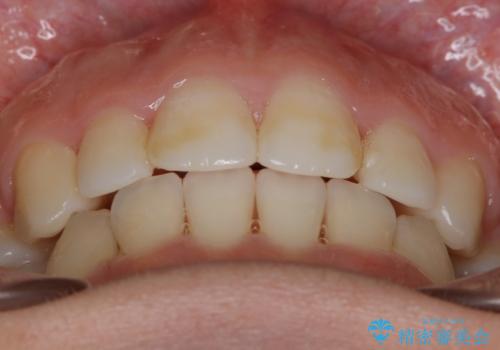

- 口元を下げたいという主訴でご来院されました。

ガタつきの度合いは軽度でしたが歯列の幅が狭く、その分前歯が上下とも前方に出てしまっていました。

しっかりと口元・顔貌まで変化を起こせるように上下左右の第一小臼歯を抜歯し、ワイヤー装置にて矯正を開始することとなりました。